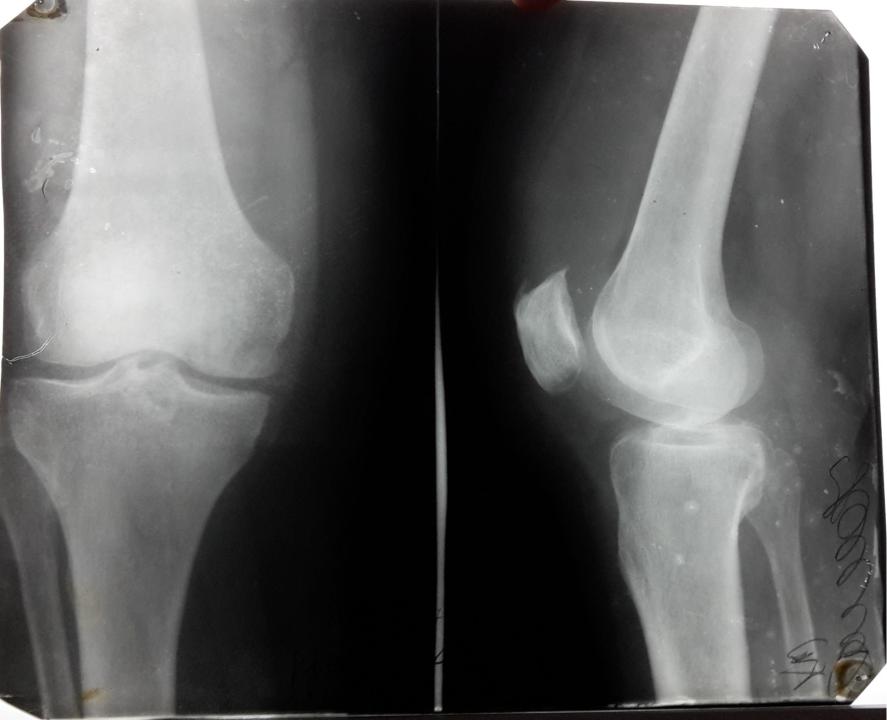

Пример деформирующего артроза коленного сустава.

Резкое сужение внутренней части суставной щели свидетельствует о полном разрушении там суставного хряща. Видны субхондральный склероз и кистозная дегенерация под суставными поверхностями.